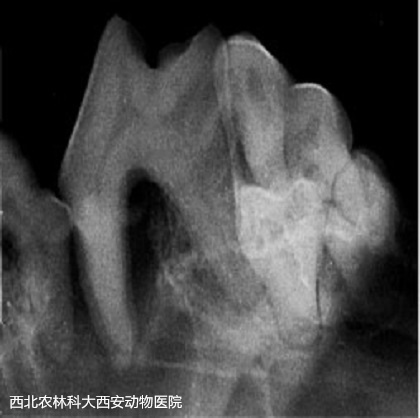

術(shù)前準(zhǔn)備:彈簧開口器撐開口腔,咽部填塞一塊紗布。檢查口腔,可見大量牙結(jié)石見(圖1)。超聲波潔牙術(shù):使用超聲波潔牙器將牙齒的齦上和齦下表面的牙結(jié)石和牙菌斑去除見(圖2)。在潔牙期間發(fā)現(xiàn)其上、下多個(gè)切齒均有松動(dòng),進(jìn)行牙科X線檢查見(圖3),并將上、下切齒各拔掉5顆。108號(hào)齒見(圖4)先前拍片提示存在口鼻瘺,采用注射器噴注可見口腔與鼻腔(右側(cè))連通,使用裂鉆將牙根分開見(圖5),并將牙根分別拔除,口鼻瘺內(nèi)存在多量粘稠惡臭物見(圖6),徹底沖洗口鼻瘺處。牙科手術(shù)刀于上黏膜瓣切出一U形切口,用縫線將黏膜瓣和腭側(cè)黏膜對(duì)合后結(jié)節(jié)縫合見(圖7)。最后,清理口腔去除咽部填塞的紗布?jí)K。術(shù)后通過靜脈輸液給予抗生素和止血藥物。術(shù)后一周每天沖洗口腔兩次,涂抹凝膠四次。一周后回訪恢復(fù)較好,口臭明顯改善,未再出現(xiàn)打噴嚏和流鼻。

圖四